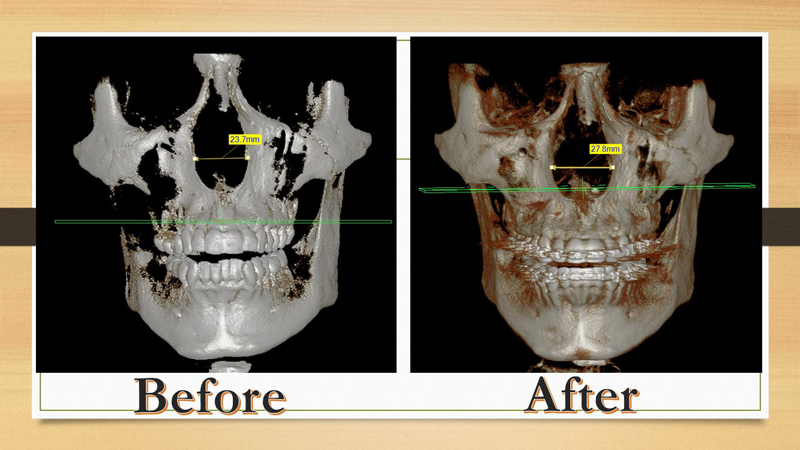

Here's the case Dr. Kanaan treated in his office with a patient who gained significant expansion in her nose, and she got rid of her mouth breathing.

Notice the above sequence of changes in her upper jaw width. The X-rays below also show her expansion and suture opening after stage one and after stage two.

This patient has been on allergy medications for years to improve their breathing. However, after watching Dr. Kanaan with Debra Duncan talking about MARPE and its benefits, he decided to undergo the MARPE procedure. Dr. Kanaan placed the MARPE with longer screws to maximize its force. His case was a complete success with over 5 mm of expansion in his basal nose level. Patient was pleased with his MARPE treatment in Houston.

Notice the excellent expansion on the X-ray and how it was filled with bone.